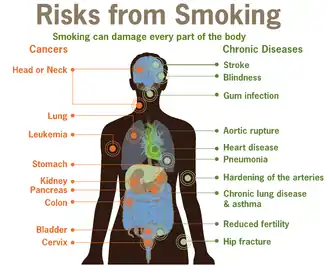

Tobacco smoking, most often associated with "coffin nails," or cigarettes of the tobacco plant (Nicotiana tabacum), is a foul, expensive, unhealthy habit that stains your fingers and teeth, costs a fortune, "harms nearly every organ of the body" and causes or increases the risks of a staggering amount of diseases below:[2]

- cancer of the lungs (most cases), and some cancers of the bladder, blood (acute myeloid leukemia), cervix, colon and rectum, esophagus, kidney and ureter, larynx, liver, oropharynx, pancreas, and stomach

- cardiovascular disease, including stroke

- asthma

- chronic obstructive pulmonary disease [COPD] (formerly called chronic bronchitis or emphysema)

- reproductive risks (preterm birth, stillbirth, low birth weight, sudden infant death syndrome, ectopic pregnancy, orofacial clefts, reduced sperm quality)

- lower bone density

- tooth and gum disease

- cataracts and age-related macular degeneration

- type 2 diabetes mellitus

- inflammation

- rheumatoid arthritis

- increased risk for short-term complications following total hip and total knee replacement